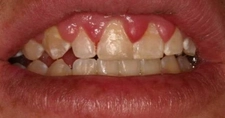

Hamilelikte Damak Yarasının Zorluğu

Eda Naz, hamilelik sırasında damak yarası yaşamak gerçekten de zorlayıcı bir durum. Özellikle lezyonların kanamalı ve ağrılı olması, günlük yaşamı ciddi şekilde etkileyebiliyor. Yeme içme sırasında ortaya çıkan ağrılar, annenin beslenmesini olumsuz etkileyebilir ve genel yaşam kalitesini düşürebilir.

Ağız Hijyeninin Önemi

Ağız hijyenine dikkat etmek ve düzenli diş hekimi kontrolleri yapmak elbette önemlidir ancak bu süreçte yaşanan rahatsızlıklar, bu kontrolleri zorlayıcı hale getirebilir. Hamilelik döneminde yaşanan hormonal değişiklikler, ağız sağlığını etkileyebilir ve bu da ek sorunlara yol açabilir.

Hormonal Değişikliklerin Etkisi

Hormonal değişikliklerin bu tür durumlara neden olduğunu bilmek, birçok anne adayı için bir nebze rahatlatıcı olabilir. Ancak, bu durumun getirdiği rahatsızlık hissi, kaygı ve endişeleri de beraberinde getiriyor olabilir. Hamilelik sürecinde yaşanan fiziksel zorluklar, duygusal olarak da etkileyici olabilir.